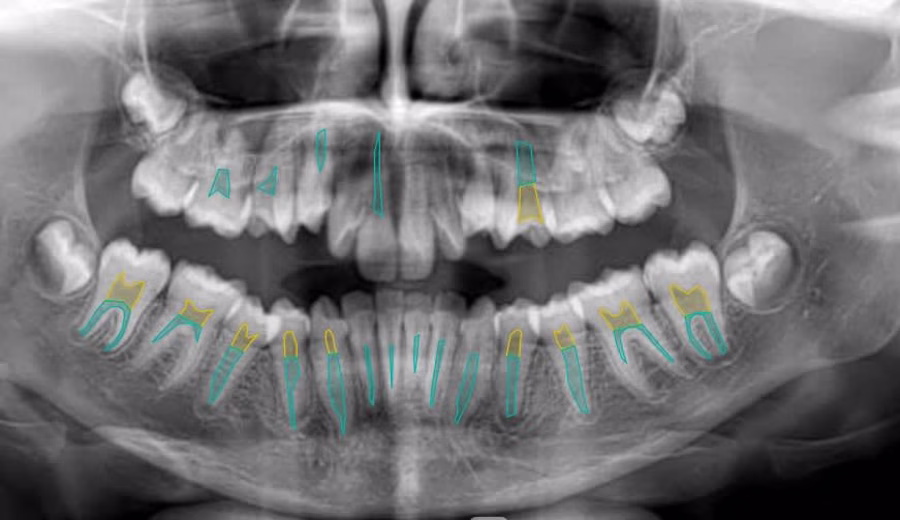

Annotated complex dental X-ray medical imaging datasets used to train AI models for healthcare applications.

The project involved precise labeling of anatomical structures including teeth boundaries, roots, and surrounding regions using polygon and keypoint annotation techniques.

The objective was to generate high-quality training datasets that allow machine learning systems to accurately detect dental structures and support medical imaging analysis.

Responsibilities included: • Image segmentation and polygon annotation • Keypoint labeling for anatomical structures • Dataset preparation for machine learning models • Annotation quality control and validation